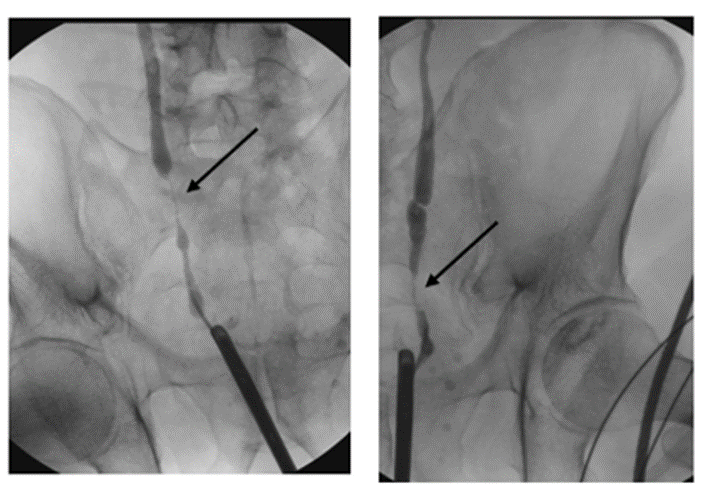

The patient underwent an elective diagnostic cystoscopy and TURBT. The diagnostic cystoscopy (see Figure 1) showed diffuse erythematous and edematous bladder mucosa without any distinct papillary or nodular suspicious lesions. Random cold biopsies and targeted warm biopsies of the erythematous regions were obtained. Retrograde ureteroscopy was not possible; therefore, a retrograde ureterography (see Figure 2) was performed, which showed bilateral distal ureteral stenosis approximately 3 cm proximal to the ureteric orifices, raising suspicion of external compression.

Figure 2: Retrograde ureterography showing bilateral distal ureteral stenosis